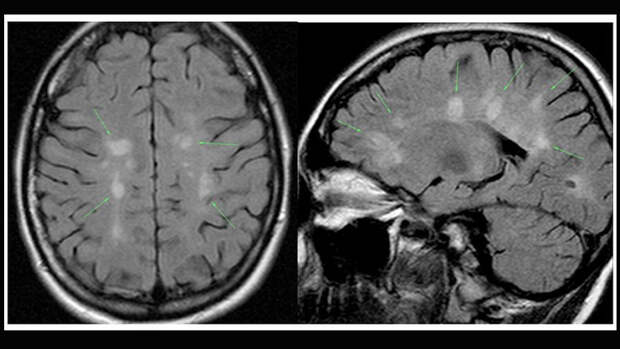

Выявление рассеянного склероза на ранней стадии позволяет замедлить прогрессирование заболевания и предотвратить раннюю инвалидизацию больных, добавляет невролог. Лечение включает медикаментозную и физиотерапевтическую терапии, а также и программы индивидуальной нейрореабилитации.